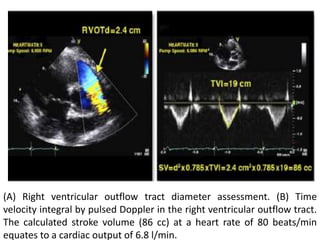

(A) Right ventricular outflow tract diameter assessment. (B) Time

velocity integral by pulsed Doppler in the right ventricular outflow tract.

The calculated stroke volume (86 cc) at a heart rate of 80 beats/min

equates to a cardiac output of 6.8 l/min.